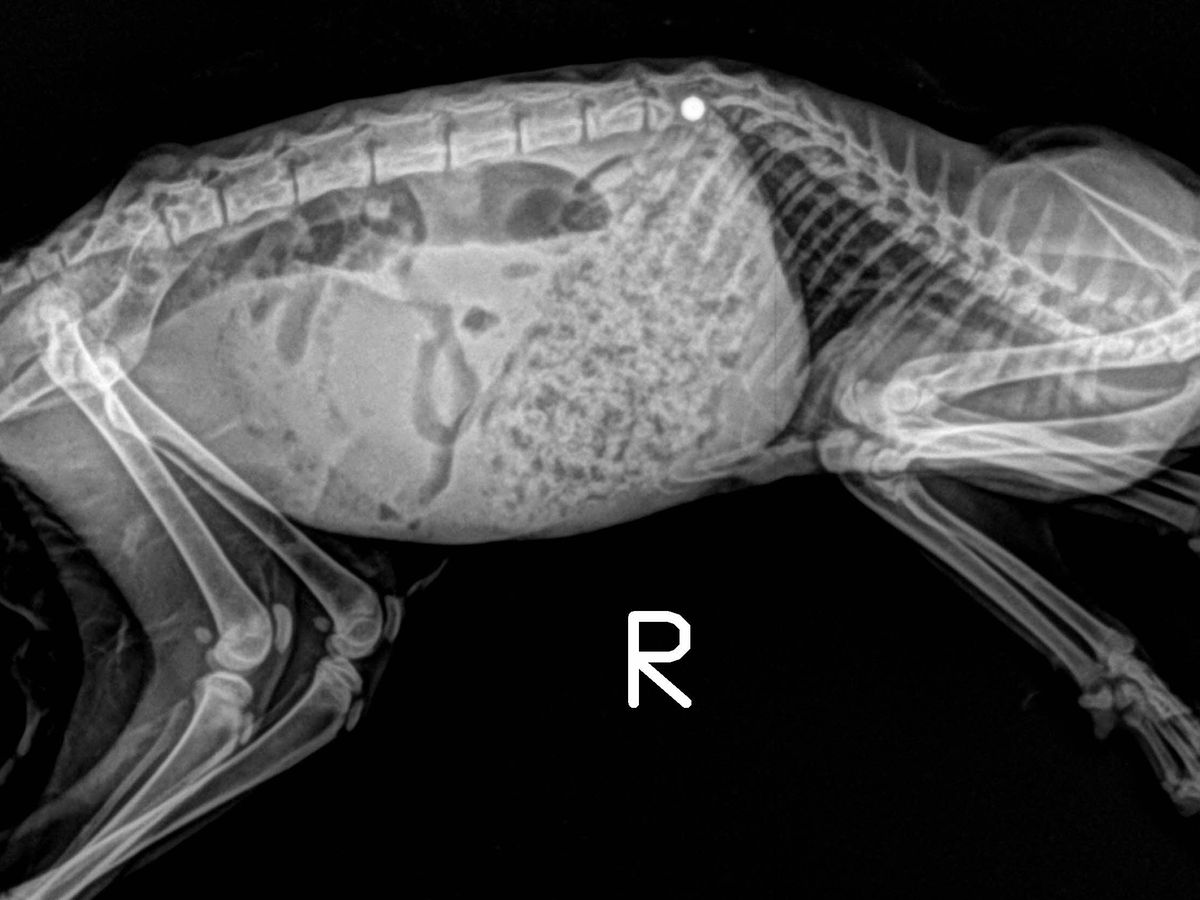

Yesterday late afternoon I got a message from a fellow rescuer about a kitten in need at a shelter I don’t usually pull from. I got the medical info from them. They said she was shot in the spine but had deep pain response, was Defecating but not urinating. I spoke with Dr Levine’s office and I was told if she was actually moving and had deep pain response there was a decent prognosis. If they were wrong it was about a 10% chance. I had to make all these decisions and calls in under an hour. So I decided to go for it because worst case is she winds up continuing to be paralyzed in the back end.

Well I got Felicity and she only has reflexes, no pain response. So she has the lower chance of ever becoming normal again. Not to say it won’t happen, but Dr Levine has to give me a fair prognosis but he knows I will do everything for her.

Felicity is going in to see Dr Levine tomorrow morning for surgery to remove the projectile in her spine. The hope is with this object removed everything will heal/the spinal cord will return to normal and Felicity will be fine. I don’t know the cost of this yet, if he wants to do an MRI, etc. But spinal surgery is never cheap. I’m estimating $5800-7200 for surgery with another possible $2000 for MRI. I’ll ask them to put an estimate together today. But for today Felicity is heading to see Dr Sabshin for some bloodwork, a urinalysis (her pee STINKS and she has pus coming from her vagina), and a felv/fiv test.